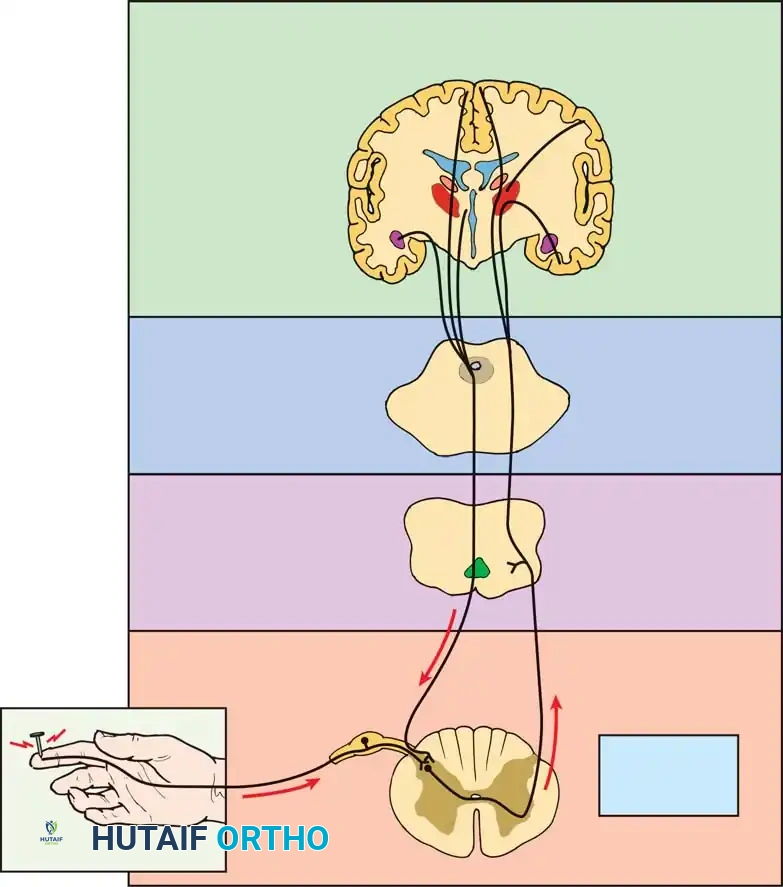

Understanding the complex interplay between peripheral nociception and central pain modulation is critical for rational treatment. Pain signals travel via C-fibers and A-delta fibers to the dorsal horn, ascending through the spinothalamic tract to supraspinal centers where complex psychosocial modulation occurs.

Midbrain

Fig. 39-44 Main anatomical areas of pain modulation. The interplay between peripheral nociception and supraspinal modulation dictates the clinical perception of discogenic pain.